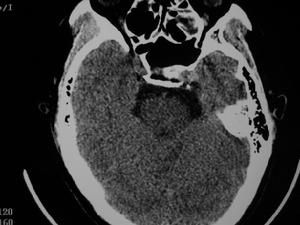

1、眼部檢查:患眼瞳孔常散大,直接光反應遲鈍或消失,間接光反應存在。單眼受累的患者通常出現相對性傳入性瞳孔功能障礙(RAPD)。該體徵表現為:患眼相對於健眼對光反應緩慢。尤其在檢查者將光線在兩眼之間交替照射時,患眼的瞳孔直徑比健眼大。眼底檢查,視乳頭炎者視盤充血(如圖)、輕度水腫,視盤表面或其周圍有小的出血點,但滲出物很少。視網膜靜脈增粗,動脈一般無改變。球後視神經炎者眼底無異常改變。

3、顱內腫瘤特別是蝶鞍區占位性病變,早期可呈球後視神經炎改變,視野及頭顱X線有助診斷。頭顱CT及MRI更有助於早期發現。